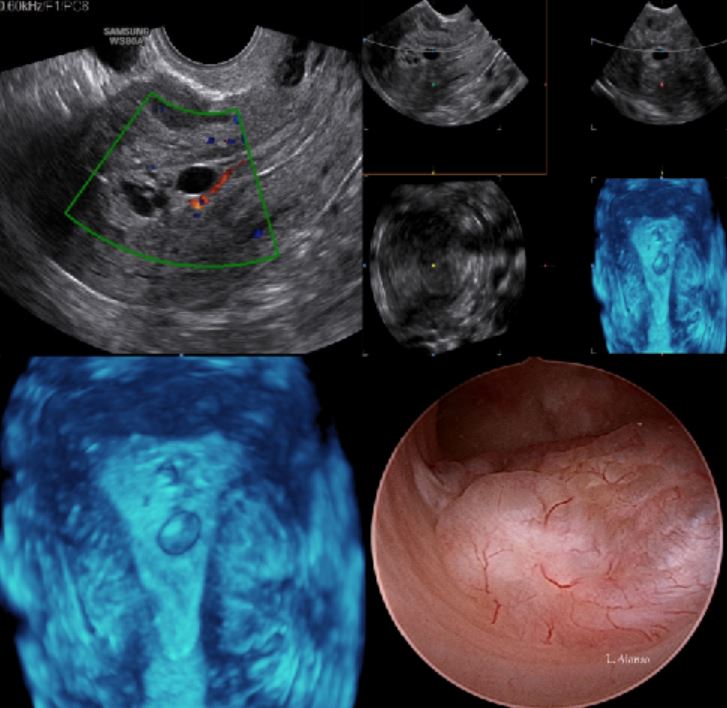

The primary tool for initial diagnosis of endometrial polyps is transvaginal ultrasonography (TVUS). Endometrial polyps appear as a hyperechogenic lesion with regular contours. Cystic glands may be visible within the polyp. Endometrial polyps are seen as a focal mass or nonspecific thickening of the endomeytrium. These findings, however, are not specific to polyps as leiomyomas (fibroids) particularly submucosal forms may have the same features.

Compared to 2D ultrasonography (TVUS), 3D TVUS with color-flow Doppler has a higher diagnostic accuracy by enhancing endometrial and sub-endometrial vascularization indices; moreover combining endometrial echogenicity, thickness, and volume with 3D TVUS is better than single measurements with 2D TVUS for detecting endometrial polyps.

Among the diagnostic methods for investigating endometrial disease, hysteroscopy has the highest diagnostic efficacy. Hysteroscopy with guided biopsy represent the gold standard in the diagnosis of endometrial polyps (Figure 4). The main advantage of hysteroscopy is the ability to visualize and remove polyps concurrently.

It is important to include in the hysteroscopic evaluation of endometrial polyps some characteristics such as: number, size, location, consistency, vascularization and implant base, all characteristics that can be achieved by the gold standard of hysteroscopy.